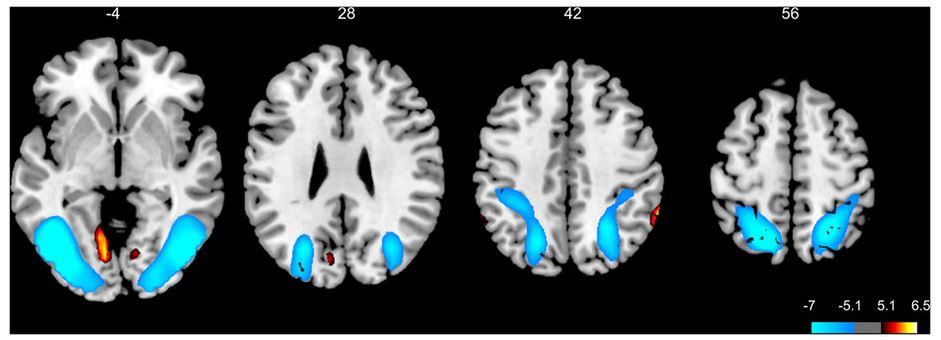

За селективное внимание в нашем мозге отвечает так называемая Задняя (пространственно-зрительная) система внимания. К ней относятся области передней поясной коры, префронтальная дорсолатеральная область и хвостатое ядро. Эти области мозга сообщаются между собой с помощью нейротрансмиттера норадреналина. С помощью данного механизма мы можем фильтровать стимулы и расставлять приоритеты, классифицируя их по степени важности как мета-цели либо внешние стимулы (релевантные и отвлекающие). Всё это возможно благодаря ингибиции ненужных стимулов.